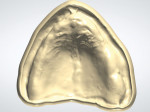

The final design data from the scanned impressions and try-ins were merged and the arches were aligned in the CAD software. Virtual models of the maxillary and mandibular arches were then created (Figure 8 and Figure 9). The virtual models were oriented in the proper VDO and CO positions as established by the scanned try-ins and bite registrations to allow design of the final prosthetics in the optimal orientations (Figure 10). The initial denture tooth positions from the try-in were adapted to the master impression surfaces and final tooth positions that were established during the clinical try-in and bite registration, which were incorporated into the digital design (Figure 11 through Figure 13).